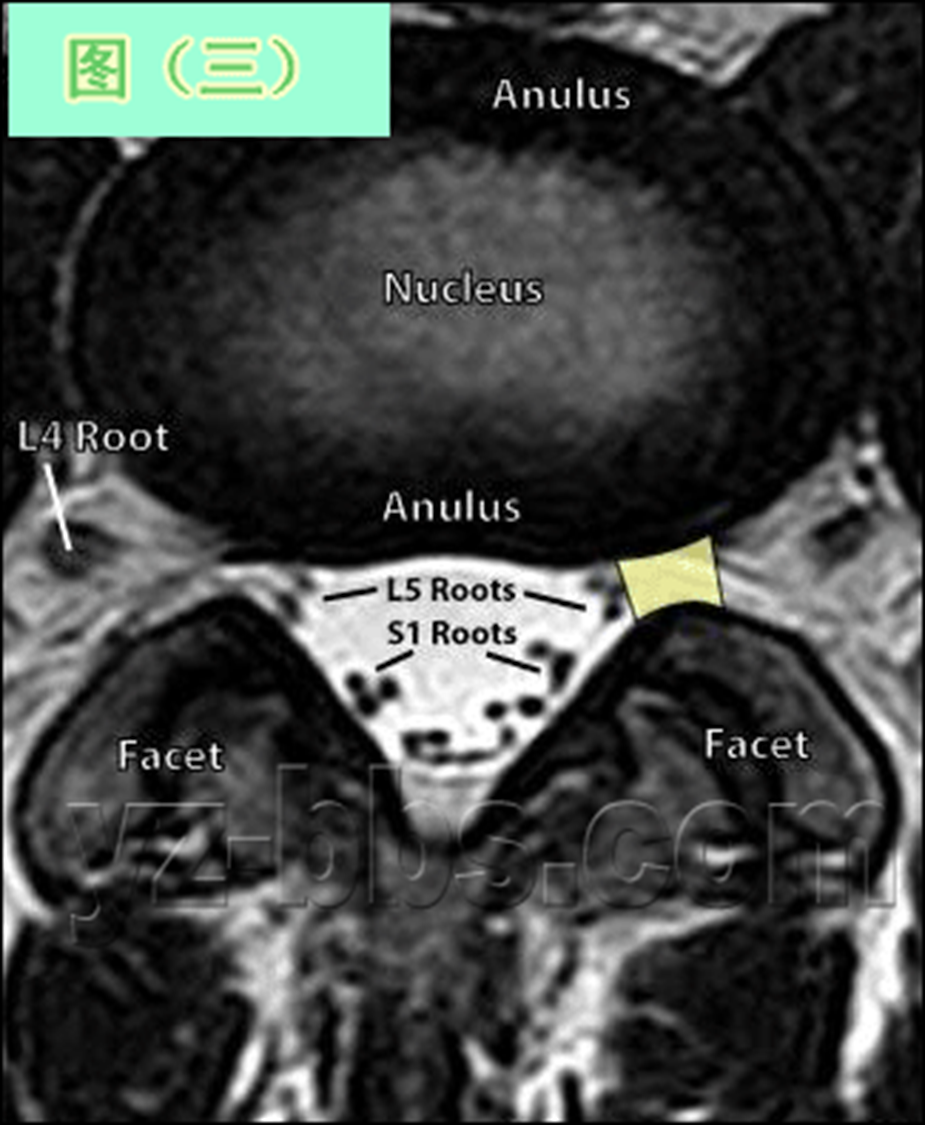

一个健康的45岁男性的L4椎间盘的轴状面观。

髓核区及周围的纤椎环区。

靠近L5神经根的椎间盘后缘的凹度,这是正常健康椎间盘的象征。

L4发出神经根更靠侧方一点。这就不难理解为什么如果有大的椎间盘突出或椎管狭窄,发出神经根L4及过往神经根L5将同时受压。

在此图中,可清楚地看到悬挂在硬膜囊内的细小的神经根(L5神经根及S1神经根),它们以不完全有绪地状态排列着。注意,神经孔是很开阔的(浅黄色区),表明没有因邻近椎间关节问题形成在的椎管狭窄。T2加权象对于察看退化性椎间盘病是最好的,因为T2像将富含水份的结构表现为亮白色, 含水少的区域表现为黑色。